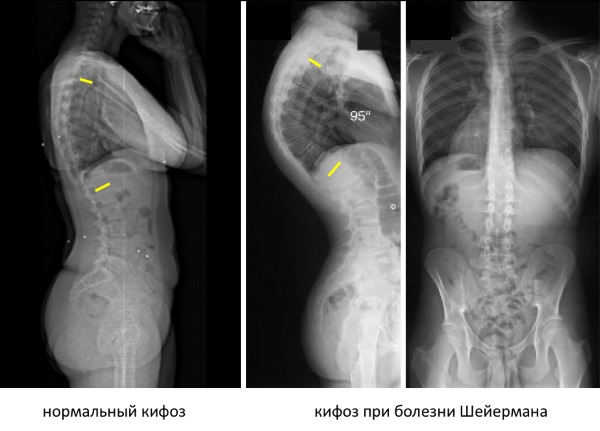

После первичного осмотра вам будет назначена рентгенография, которая поможет определить степень деформации и стадию заболевания.

Так выглядит болезнь Шейермана-Мау на рентгеновском снимке.